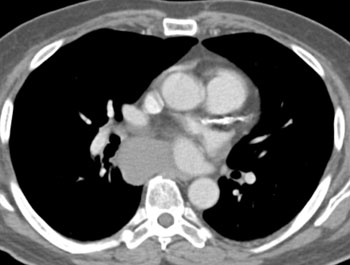

Question 5: 47 year old male with mass discovered on CT during chest pain workup. What is the diagnosis?

Diagnosis: Pericardial cyst

Pericardial Cysts: CT Findings

• Smoothly marginated lesion surface

• Less than 10 HU

• No enhancement on contrast studies

• Size range from 2-30 cm

• Usually incidental finding in an asymptomatic person